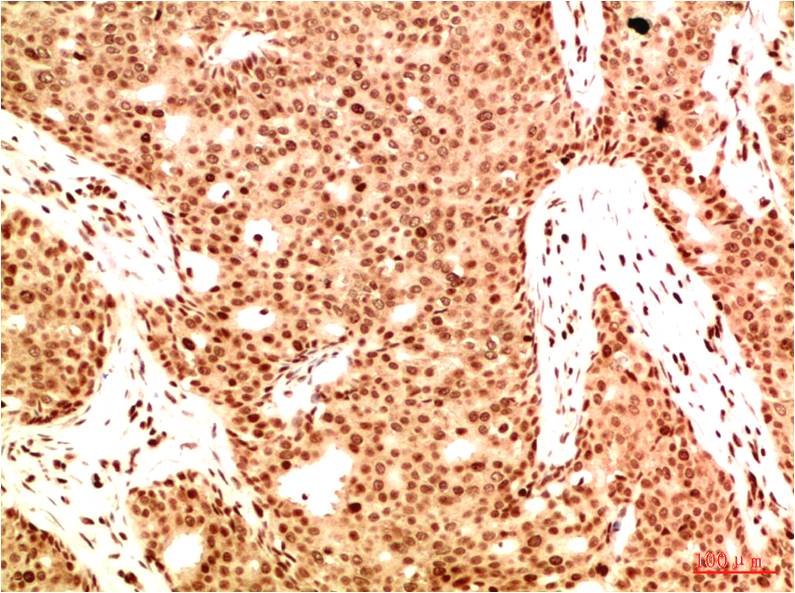

分类: 科研抗体货号: P20021别名: Antigen NY-CO-13; Cellular tumor antigen p53; Phosphoprotein p53; TP53; Tumor suppressor p53应用: WB,IP,IF反应种属: Human,Mouse,Rat